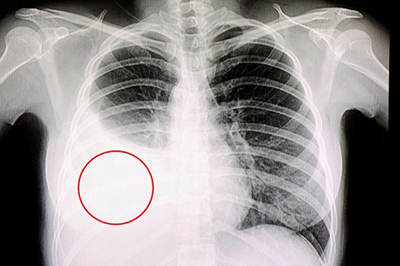

右侧大量胸腔积液X线胸片

在系统抗结核治疗基础上配合胸腔穿刺抽取胸腔积液是目前治疗结核性胸膜炎的常规治疗方法,但是部分患者胸腔积液吸收不良出现胸膜增厚、胸膜粘连、肺组织局部膨胀不全,从而导致肺功能受损、并且可伴有不同程度的胸痛,影响患者的预后生活质量和身体素质,尤其是对于青、中年这一主要的劳动力群体。据报道在所有结核性胸膜炎患者中,有20%-50%可发生2-10mm的残余胸膜增厚,并且在发病后5-7天即可形成,临床预后不良率可达15.2%,严重者可致胸廓变形塌陷、肺不张。